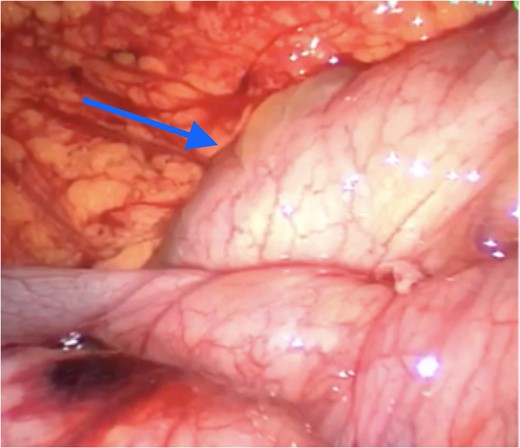

Laparoscopy revealed an accessory intra-abdominal cyst encapsulating the entire length of small bowel (Fig. 2) and the large bowel to the mid-transverse colon.

Peritoneal encapsulation cyst with small bowel contents at the bottom of the figure. Arrow demonstrates the attachment of the sac to the posterior abdominal wall peritoneum. Note the morphological similarity between the sac of the peritoneal encapsulation (bottom) and normal abdominal peritoneum (top).